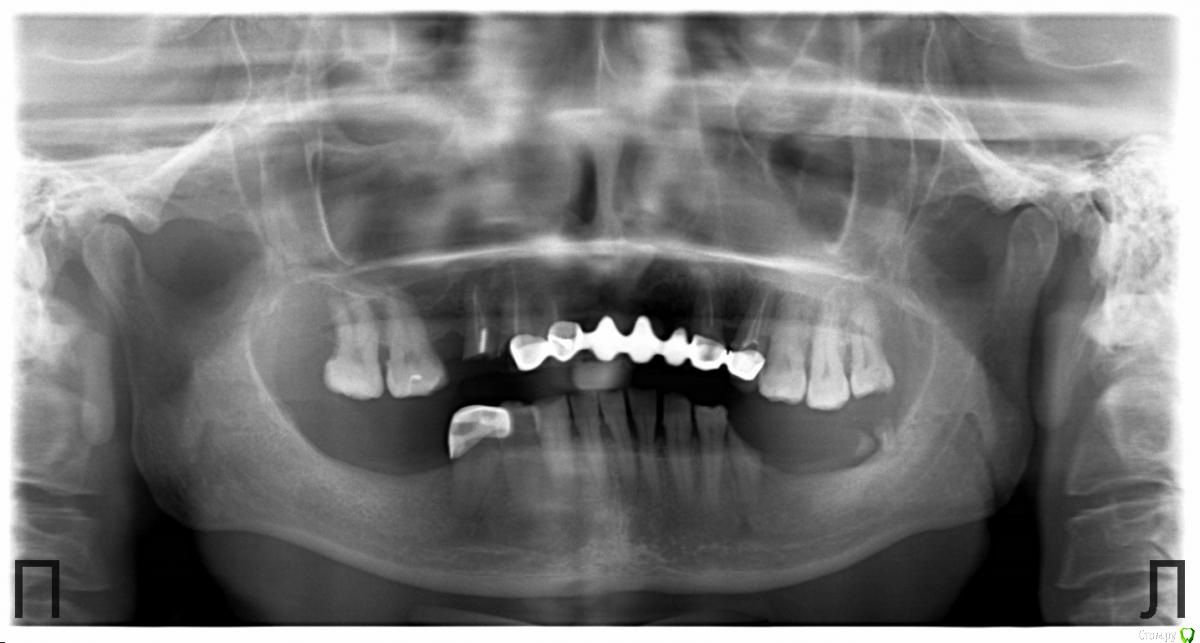

Витторио Орлионе Опубликовано 12 декабря, 2016 Поделиться Опубликовано 12 декабря, 2016 Здравствуйте, уважаемые форумчане. Поделитесь пожалуйста своим мнением и опытом вот по такому случаю: пациентка 40 лет обратилась с жалобами на подвижность мостовидного протеза и хочет реабилитации. Импланты позволить себе не может и очень хочет несъёмную конструкцию. Пожалуй самый главный вопрос: что целесообразней: перелечить те из опорных зубов, которые ещё можно сохранить и покрыть их коронками или удалить все корешки и восстановить их уже в съёмном протезе? Возможно ли использовать эти корни для лучшей фиксации протеза во рту и как? Ссылка на комментарий

chervoncevdaniil Опубликовано 12 декабря, 2016 Поделиться Опубликовано 12 декабря, 2016 Да таких большинство,которые импланты не могут позволить,но очень хотят несъемную .Тут конечно съемники,но окклюзионная плоскость-печаль,там дистально внизу место то есть под что нибудь?или только верх обсуждаете? Ссылка на комментарий

4ebstom Опубликовано 12 декабря, 2016 Поделиться Опубликовано 12 декабря, 2016 16,17.26,27,28 настолько опустились,что и для гарнитурных тут места нет( Феномен никто не отменял) Ссылка на комментарий

RuStom Опубликовано 13 декабря, 2016 Поделиться Опубликовано 13 декабря, 2016 На верхней челюсти 3 класс по Кеннеди. Ссылка на комментарий

chervoncevdaniil Опубликовано 13 декабря, 2016 Поделиться Опубликовано 13 декабря, 2016 Даниил, речь о протезировании низа была лишь слегка задета, но вот теперь понимаю что он пожалуй первостепенен. Я понимаю, что лучше протезировать одновремненно обе челюсти, но ведь тогда на праздники пациентка останется без улыбки, так что планирую предложить начать всё таки с нижней челюсти. Подскажите а какой оптимальный срок после удаления зубов надо выдержать перед снятием оттисков?Вообще в идеале месяц,но я жду недельки 2.5-3 и приглашаю на консультацию,потому что там могут быть всякие экзастозы и костные выступы после удаления,которые приедтся сгладить хирургически.Я к чему веду,если вы сделаете только верх,например в ее привычном прикусе,а потом решите делать низ,то нормальной окклюзии вы не получите из-за зубоальвеолярного удлинения,тут как минимум нужно боковые зубы укорачивать и одевать коронки,либо вообще вопрос о удалении стоит(по панораме сложно судить насколько они выдвинулись)и возможно вам прикус поднимать придется,а для этого нужно делать сразу обе челюсти Ссылка на комментарий

Витторио Орлионе Опубликовано 13 декабря, 2016 Автор Поделиться Опубликовано 13 декабря, 2016 Сегодня мостик сняли и вот что под ним было. А что касается верхних моляров, то 2.8 весь в кариесе, 2.7 уже с 1 степенью подвижности, и выдвинулись они там мм на 3 что в 1м, что во 2м сегменте.пожалуй стоит задуматься о пспп. Ссылка на комментарий